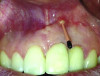

Patient 1: A 30-year-old female patient with an unremarkable medical history presented with implant No. 9 exhibiting retrograde peri-implantitis. Tooth No. 9 had been replaced with the implant 8 years prior because of a history of trauma and failed root canal treatment. The implant exhibited a periapical radiolucency with the sinus tract tracing to the apex of implant No. 9 (Figure 1 and Figure 2). The patient had a high smile line with longer clinical crowns at Nos. 9 and 10 compared with Nos. 7 and 8 (Figure 1 and Figure 2).

Fig 1 and Fig 2. Case 1: Initial clinical presentation with gutta-percha placed in the apical fistula of tooth No. 9 (Fig 1); radiograph showing gutta-percha point leading to the periapical lesion (Fig 2).

Figure 1

Figure 2